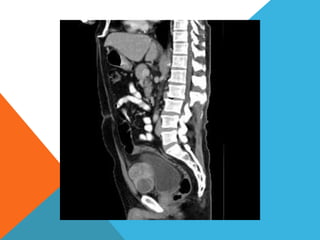

El paciente presentó síntomas de sangrado digestivo y pérdida de peso. Exámenes revelaron gastritis crónica asociada a H. pylori. Un tumor fue descubierto en una colonoscopia normal. La cirugía removió un tumor fibroide solitario, una rara neoplasia mesenquimal que usualmente crece lento y tiene bajo potencial de malignidad. El pronóstico después de la remoción quirúrgica es generalmente bueno.